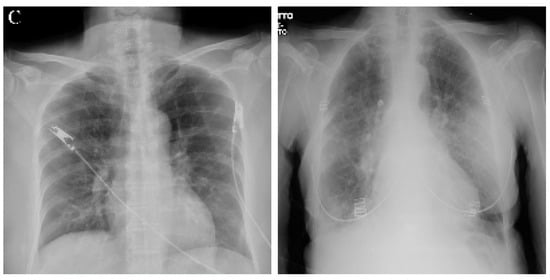

Figure 8 and Figure 9 display four original pulmonary radiographs—two of patients diagnosed with COVID-19 and two of uninfected people. Each of these images was properly predicted with the derived classifier. For each of these images, the corresponding SHAP values were computed, and the results are illustrated in Figure 10, Figure 11, Figure 12 and Figure 13.

Figure 8. Examples of radiography images of patients infected with COVID-19 (positive examples).